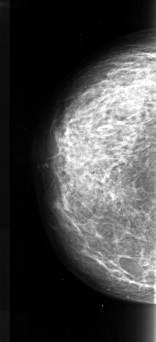

A_1023_1.LEFT_MLO

LEFT_MLO LINES 5431 PIXELS_PER_LINE 2386 BITS_PER_PIXEL 16 RESOLUTION 42 NON_OVERLAY